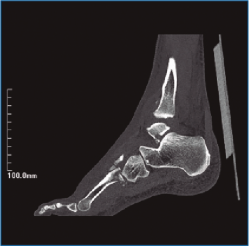

La evolución clínica y radiológica ha sido satisfactoria, permitiendo un aumento progresivo de las actividades (Figuras 6 y 7). A los 2 años de seguimiento el paciente no refiere limitaciones, con una puntuación en la escala de la American Orthopaedic Foot and Ankle Society (AOFAS) de 90.

Figura 7. Imagen de tomografía computarizada al año de la cirugía.